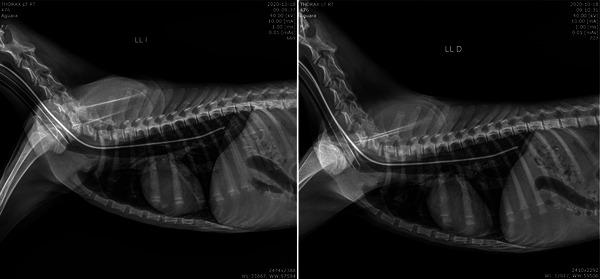

The maned wolf, Chrysocyon brachyurus, is the largest South American canid, with a natural distribution that stretches across Peru, Bolivia, Brazil, Argentina, Paraguay and Uruguay. The present study reports the case of a rescued specimen of maned wolf that underwent a rehabilitation process in Paraguay, starting in October 2020 with its rescue, and finalising in May 2021 with the reintroduction. Herein, we document findings regarding the general management, biometrics, feeding and environmental enrichment; chemical immobilisation and monitoring; haematology, blood biochemistry and specific serology-relevant pathogens; skin examination and bone marrow cytology; orthopaedic, ophthalmological and dental evaluation; abdominal and cardiac ultrasonography; radiology and copro-parasitology. Main findings include the feeding habits of the individual and enrichment opportunities. The animal weighed 7 kg on arrival, with an estimated age of 5 months, and 18 kg on reintroduction, with an estimated age of 1 year. The animal tested negative to serologic tests for Brucella canis, Dirofilaria, canine distemper, Toxoplasmosis and canine parvovirus. Leptospira testing showed antibodies against L. grippotyphosa on both samplings, L. wolffi and L. ictero on the first sampling, and L. pomona on the second sampling. Abdominal organs were examined and measured through ultrasound evaluation and kidneys showed no alterations. Echocardiography showed preserved mitral, tricuspid and aortic valve flows, but turbulent pulmonary valve flow. Copro-parasitology reported the presence of Lagochilascaris sp. and Balantidium sp. All the information gathered aided in diagnosing the health status of the individual, and the response to environmental enrichment helped assess the behaviour, which led to the suggestion of reintroducing the animal. These data constitute the first published health check of a maned wolf in Paraguay, which can contribute to the species' conservation in the country. The protocol presented in this study can serve as a basis for developing an action plan for the maned wolf in Paraguay.

鬃狼,Chrysocyon brachyurus,是最大的南美犬科动物,其自然分布范围横跨秘鲁、玻利维亚、巴西、阿根廷、巴拉圭和乌拉圭。本研究报告了一只获救的鬃狼标本的情况,该标本于 2020 年 10 月开始在巴拉圭接受康复治疗,最终于 2021 年 5 月完成了重新引入。在此,我们记录了关于一般管理、生物统计学、饲养和环境丰富度;化学固定和监测;血液学、血液生化学和特定血清学相关病原体;皮肤检查和骨髓细胞学;骨科、眼科和牙科评估;腹部和心脏超声检查;放射学和粪便寄生虫学。主要发现包括个体的饮食习惯和丰富机会。该动物到达时体重为 7 公斤,估计年龄为 5 个月,重新引入时体重为 18 公斤,估计年龄为 1 岁。该动物血清学检测犬钩端螺旋体、犬心丝虫、犬瘟热、弓形虫和犬细小病毒均为阴性。钩端螺旋体检测显示,两次采样均对 L. grippotyphosa 抗体呈阳性,第一次采样对 L. wolffi 和 L. ictero 抗体呈阳性,第二次采样对 L. pomona 抗体呈阳性。通过超声评估检查和测量了腹部器官,肾脏无异常。超声心动图显示二尖瓣、三尖瓣和主动脉瓣血流正常,但肺动脉瓣血流有湍流。粪便寄生虫学报告存在 Lagochilascaris sp. 和 Balantidium sp. 所有收集到的信息都有助于诊断个体的健康状况,环境丰富度的反应有助于评估行为,这导致了重新引入该动物的建议。这些数据构成了巴拉圭首例发表的鬃狼健康检查,有助于该物种在该国的保护。本研究提出的方案可以作为巴拉圭鬃狼行动计划的基础。